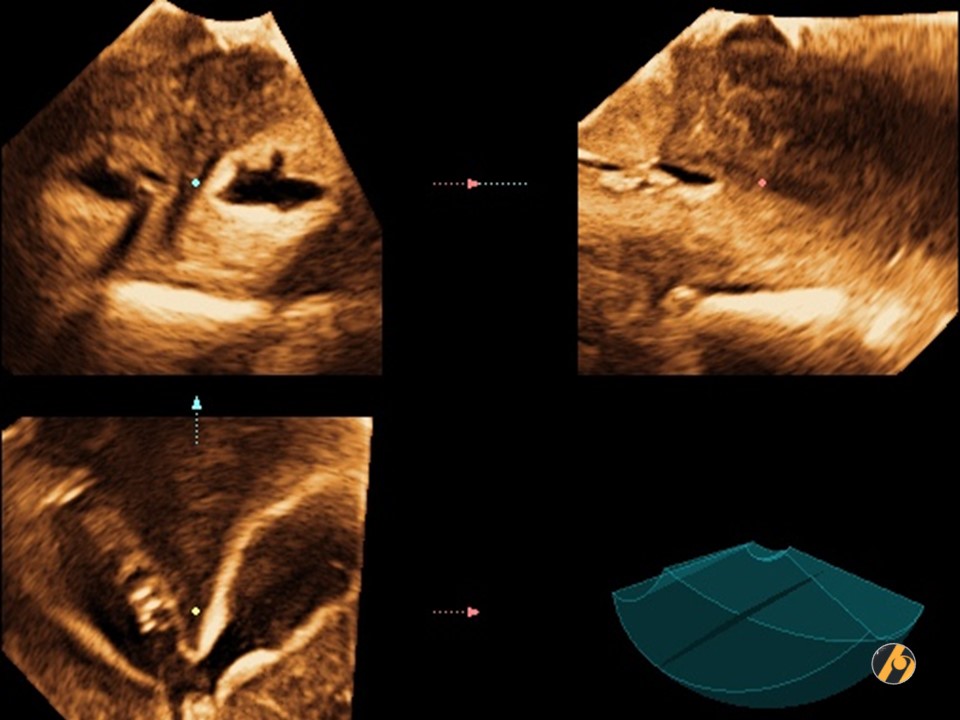

3D ultrazvuk / Multiplanarni prikaz

3D prikaz maternice u 3 ravnine, kao i rekonstrukcija slike maternične šupljine. Maternična šupljina / kavum maternice, ali i vrat maternice / cerviks podijeljeni su oštrim septumom u dva potpuno odvojena dijela, pri čemu je fundus zaravnjen. Zaravnjen fundus je ultrazvučna potvrda septirane / pregrađene maternice. U ovom slučaju je nužna operativna histeroskopija i resekcija septuma prije planiranja trudnoće, pošto su otežani zanošenje i iznošenje trudnoće. Češći su spontani pobačaji i prijevremeni porod.